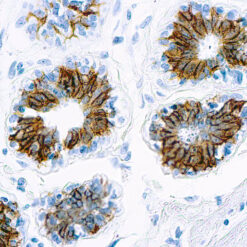

CD7 is expressed by most peripheral blood T cells, NK cells, and all thymocytes. It is one of the earliest surface antigens on T and NK-cell lineages. The antibody is a useful aid for classification of T-cell malignancies.

| Cellular Localization | Cell surface/membrane |

| Positive Control Tissue | Tonsil |

| Detection System | PolyVue™ Plus – Two Step Detection System or Montage PolyVue Plus™ Auto Detection System for Montage 360 System |